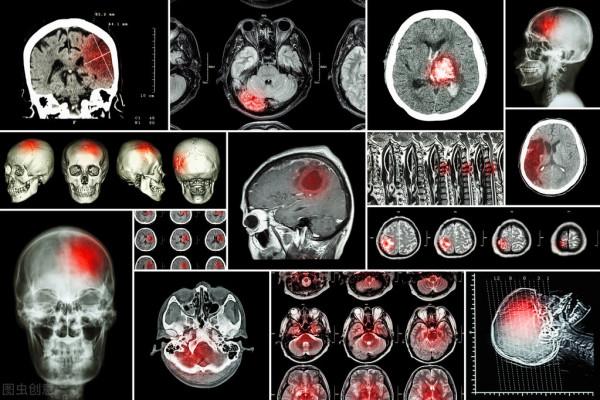

就拿腦梗死和腦出血來說吧,這兩種疾病的症狀比較相似,但是治療方案卻有很大的不同。早期腦梗死的主要治療方案是溶栓治療,而腦出血的主要治療方案是脫水、降低顱內壓,如果不做頭顱CT檢查,很多時候並不能百分百確定到底是腦梗死還是腦出血。如果病人是腦出血,而醫生診斷為腦梗死,對其進行溶栓治療無疑會增加病人的死亡率。醫學是一個比較謹慎的科學,它容不得去猜,否則後面牽涉到的可能是一場醫療事故或者一條生命!